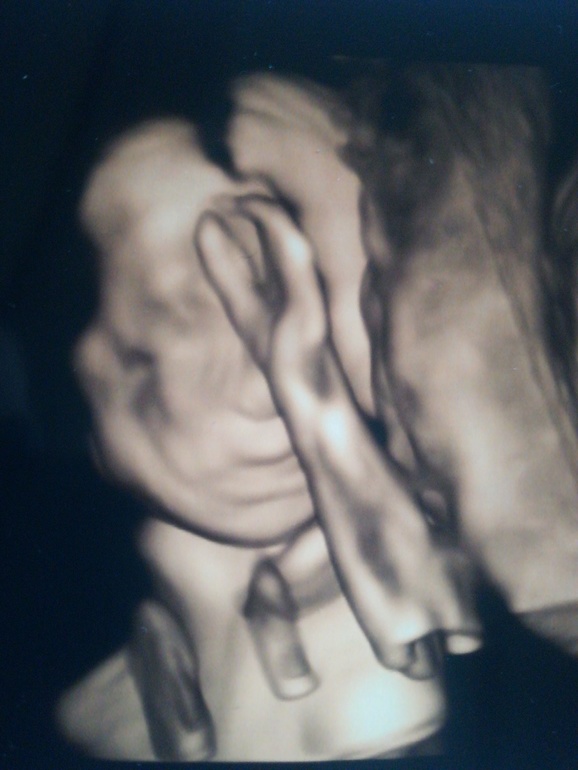

24 неделя.

Ну что, сходила я к платному врачу. Сказал сразу, что на миллион процентов у нас сын. И знаете, я оказывается так счастлива🤗😁Думала, муж расстроится, так как он дочку хотел, но нет,ни капли не расстроился💖Больше расстроились родственники, а мы счастливы 💏 Сынок наш умница, развивается как и положено, все так же на недельку опережает срок. Вес - 756 гр, положение тазовое, но так как у меня в любом случае КС, то это не имеет никакого значения. Он такой милашка там, ручкоц мне помахал👋 От врача я в восторге, все рассказал, на все вопросы ответил, успокоил. Даже 3d включил в рамках обычного приема.

Какая прелесть, вот глядя на этот комок, как можно желать что то другое. Поздравляю. 3 сына это круто!

Мы тоже недавно ходили на УЗИ! Это все так мило и волнительно! Сначала ребятенок спал, а когда проснулся закрыл лицо руками, зато своё достоинство вывалил и во всей красе показал ))))